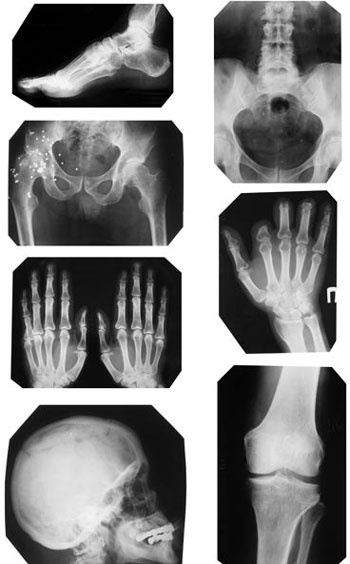

Рентгенография

Несмотря на широкое внедрение компьютерной томографии, значимым и информативным остается классическое рентгенографическое исследование.

Как правило, в поликлиниках его применяют на этапе скрининга: проще, быстрее и дешевле сделать рентгенограмму позвоночника, определиться, на каком уровне есть проблема, и затем исследовать пораженный участок прицельно с помощью магнитнорезонансного томографа.

Рентгенография остается эффективным информативным методом. С использованием ее хорошо диагностируются такие состояния, как заболевания позвоночника — дегенеративно-дистрофические (остеохондроз, спондилез, искривления), инфекционные и воспалительные (различные виды спондилитов), опухолевые заболевания. С успехом исследуются рентгенологически различные отделы периферического скелета — на предмет различных травматических (переломы, вывихи), инфекционных и опухолевых изменений. Степень тяжести остеоартроза и ревматоидного артрита определяется по рентгенологическим критериям — на рентгенограмме хорошо заметно состояние суставных поверхностей и степень остеопороза костей.

Иллюстрация к книге — Отложение солей. Диагностика и лечение [i_019.jpg]